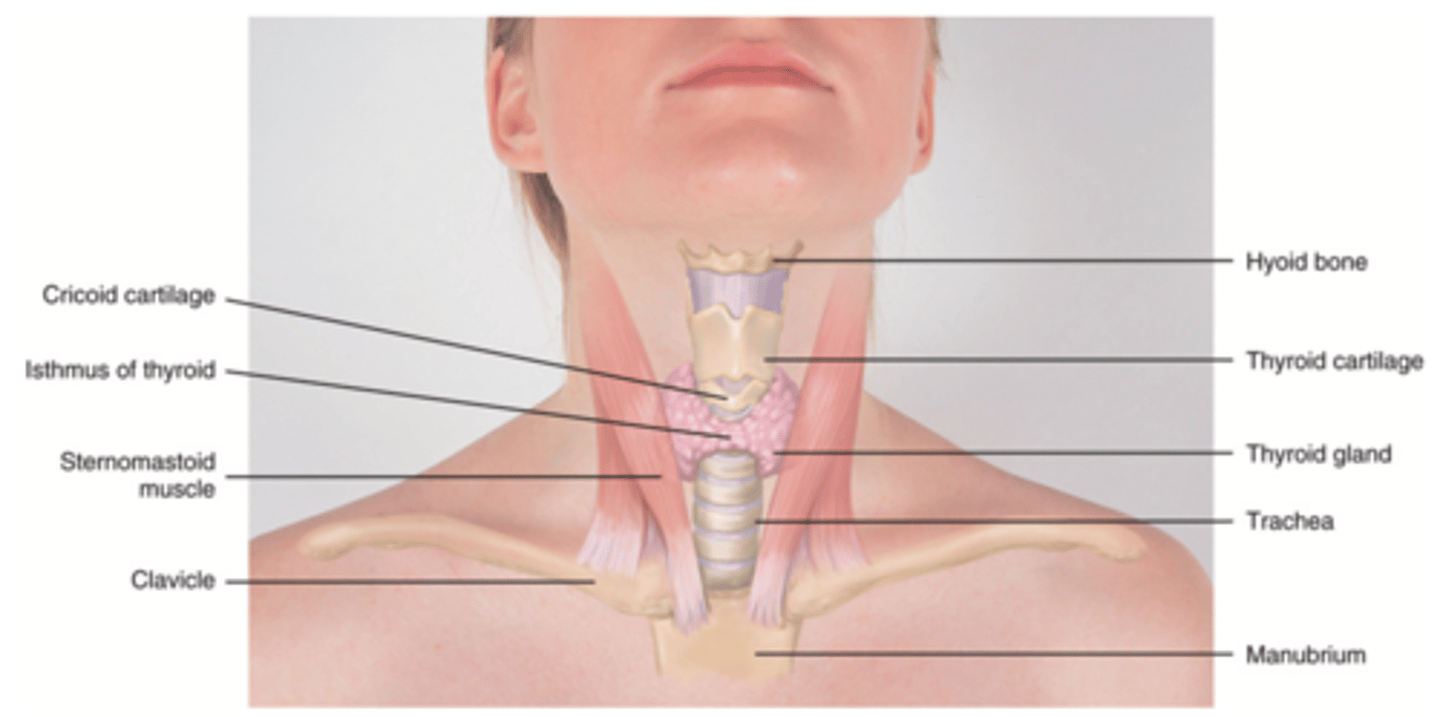

Anterior Triangle

The area that lies in front, between the sternomastoid and the midline of the body, with its base up along the lower border of the mandible and its apex down at the suprasternal notch

Posterior Triangle

The area of the neck between the sternocleidomastoid muscle and trapezius muscles

Functions of the Neck

- Continuation of the digestive and respiratory system

- Support the passage for many structures to and from the brain

Thyroid Gland

A gland found in the neck that secretes calcitonin, T3, and T4 hormones

T3 and T4 Hormones

Hormones that stimulates rate of cellular metabolism

Calcitonin

Hormone that lowers blood calcium levels

Objective Data to Assess for Neck

- Symmetry

- ROM

- Lymph nodes

- Trachea

- Thyroid gland (advanced skill; can auscultate for bruit)

(Inspect and palpate for all)

Bruit

Blowing, swooshing sound heard through a stethoscope over an area of abnormal blood flow

Key Points on Head, Face, and Neck

- Inspection and palpation are key

- Remember to assess the trachea and the thyroid